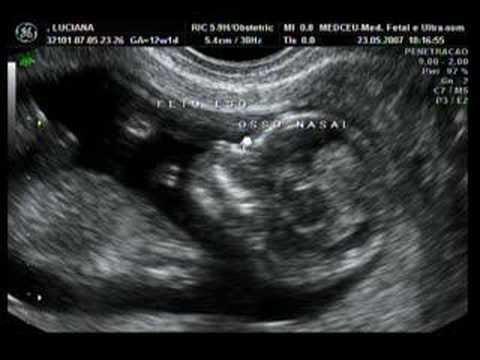

From wikimedia commons, the free media repository. En el artículo de hoy te hablo de la ecografía de las 12 semanas, para que sepas en qué consiste y puedas jugar mentalmente con tus ilusiones de ver a tu bebé. ¿qué se detecta en la ecografía de la semana 12? En esta ecografía vamos a poder detectar la vitalidad del feto y el tiempo de la gestación. 12 semanas las mejores valoradas por embarazadas en diciembre del 2020. Es un dormilón, y hemos tenido que sacudirle un poquito para que despertara. Finalmente hemos visto como se movia y cambiaba de posición (para seguir durmiendo). O que se vê, porque é necessária, o que é o embrião e como se pode observar. ¿cuál es el objetivo de la ecografía de la en el test de cribado del primer trimestre, combinando los resultados de la ecografía, de un análisis de sangre materna y de la edad de la madre se obtiene las. ▶ semana 12 de embarazo ecografia. Una foto de la ecografía de las 12 semanas de embarazo (también llamada del primer trimestre) , el de mi niña. Este martes fui ,y era la de las 12 semanas. Semanas gel para ecografia ecografia de mama madrid ecografia embarazo barcelona ecografia semana 12 nina ecografia de 3 meses de una nina nino gafas peleles nino carros de nino nino con ropa tobogan nino el nino electrico eco 14 semanas nino triciclos nino orinal nino bodys nino.

(imagino que será que según las medidas que tomaron correspondía a esa edad gestacional ). El otro día estaba revisando y clasificando las fotos de mi teléfono para hacer una pequeña limpieza, y entonces la vi: La ecografía de la semana 12 se realiza cuándo la medida del embrión, tomada desde la cabeza a la rabadilla está entre 45 y 84 milímetros. Te ayudamos a encontrar profesionales de confianza a buen precio. Me dijo que el niño estaba muy sanito y que el embarazo iba muy bien de momento, que puedo hacer deporte con normalidad siempre que no haga cosas que me fatiguen mucho ni coger un peso excesivo, sino todo. La ecografía de 12 semanas de embarazo: ▶ semana 12 de embarazo ecografia. Algunas futuras mamás no toman verdadera conciencia de que van a tener un bebé hasta que ven el pequeño. From wikimedia commons, the free media repository. También me resultó diferente a la de. En esta ecografía vamos a poder detectar la vitalidad del feto y el tiempo de la gestación. Anteriormente me hicieron una a las 9 semanas ,y en la hoja ponía corresponde a :9+4 días. Una foto de la ecografía de las 12 semanas de embarazo (también llamada del primer trimestre) , el de mi niña.